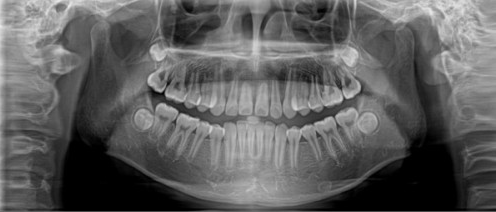

以下是崔勁松口腔金屬托槽牙齒矯正案例效果▼